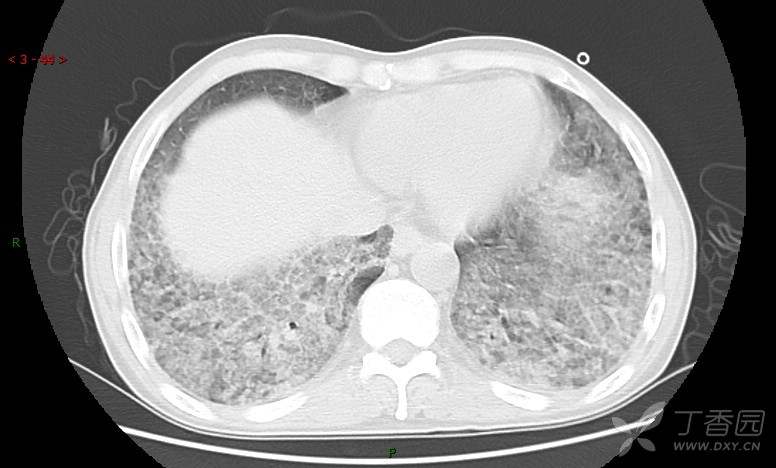

地图+铺路石征=PAP?那升高的CEA怎么说(病例3连发,附其他2例链接)

原帖名:刚入手的病例,看着都憋得慌,有PET/CT,请讨论(病例3连发,附其他2例链接)

患者男,42岁,咳嗽半年余,加重伴憋喘2月余。

血清肿瘤相关抗原116.22U/ml↑(0--95);

癌胚抗原 61.96 ng/mL ↑ 0--5

神经特异性烯醇化酶 33.12 ng/ml ↑ 0--16.3

细胞角蛋白19片段测定 40.23 ng/ml ↑ ≤3.3

肺内弥漫性网状结节影,PET-CT却无阳性病灶,这是?(附其他2例链接)